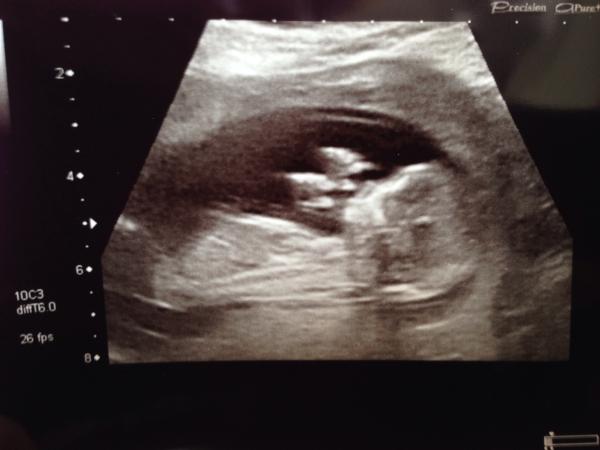

Glad everyone else's scans went well. My little wriggler would not stay still and it took ages to get any measurements or pictures! I had orange juice 45 minutes before, couldn't face two pints of just water this morning, so not sure if that did it!

Eventually got a measurement and I've moved forward 5 days, strange feeling, like I've lost a week of pregnancy, I'm sure I'll get it back at the end as DD was 13 days late!

So 13+2 apparently!

Definitely got a dancer, both hands in the air for the picture!

(The rage melted away when the image came up on the screen :-p)